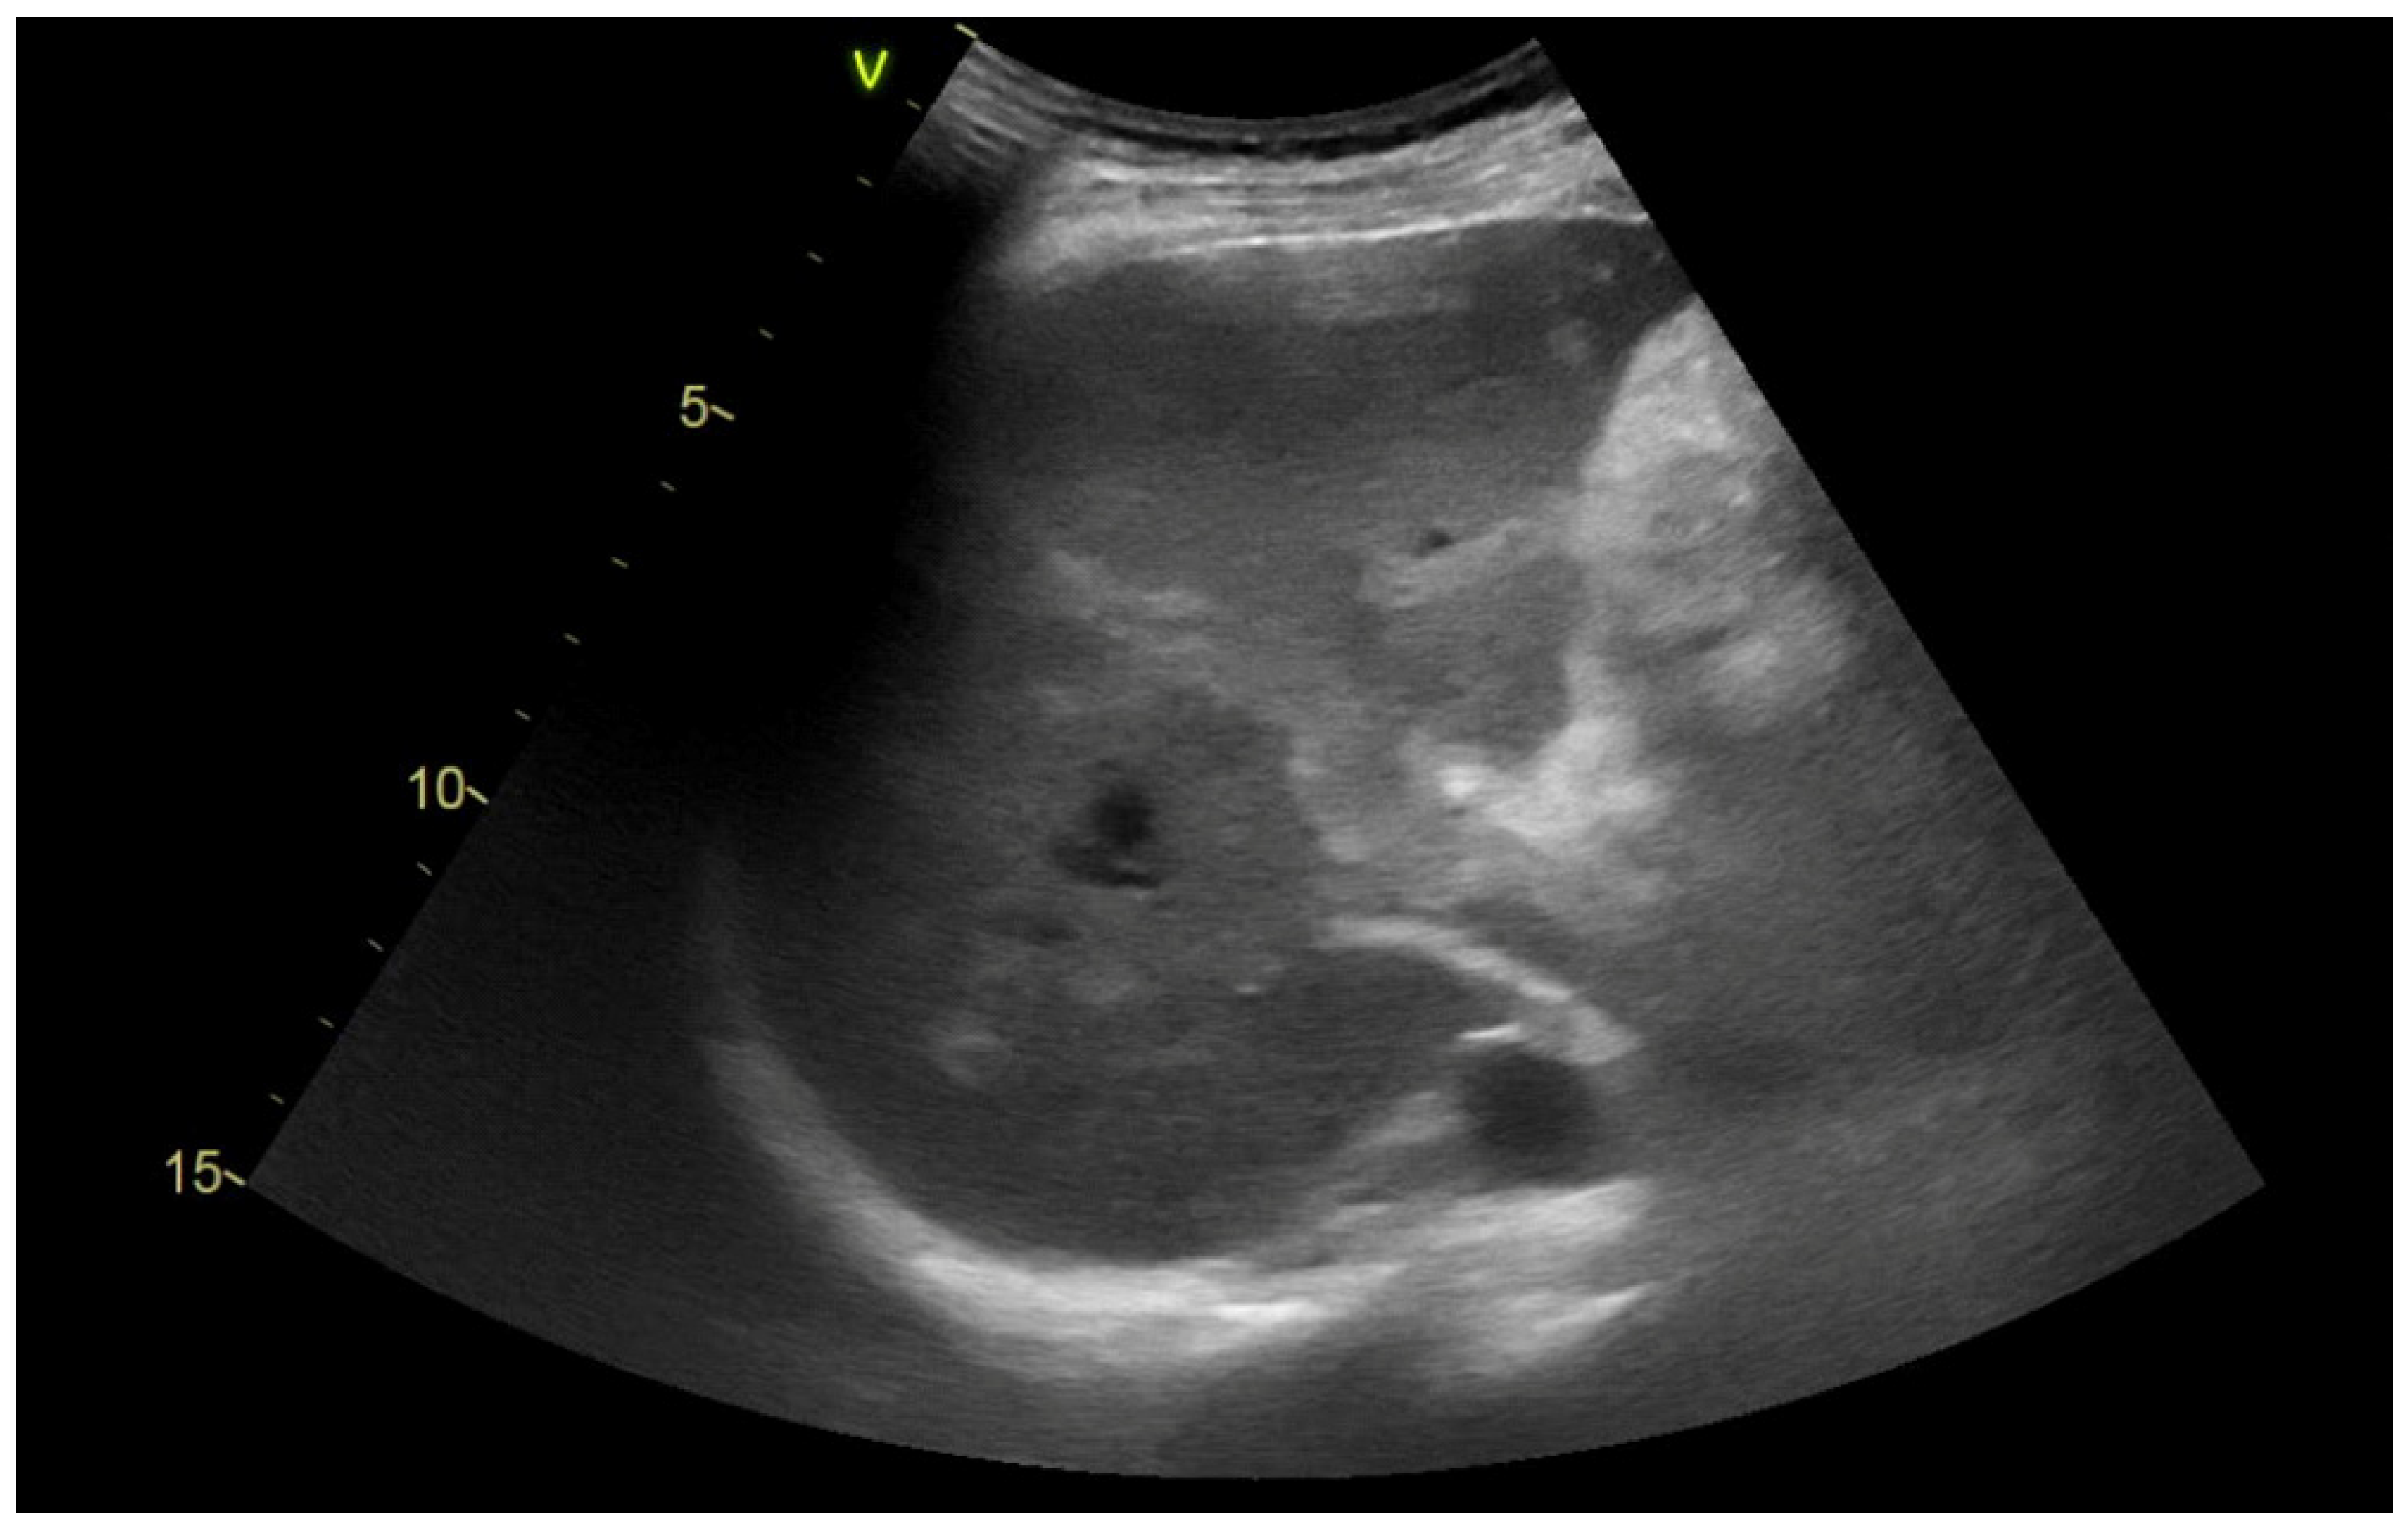

2.2. Imaging Methods